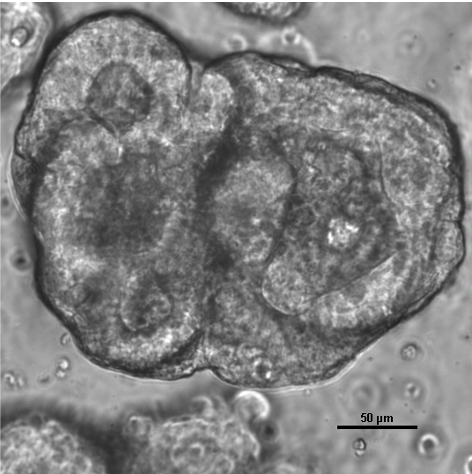

FREEZE-O (Organoid Biobank) – Specialized biobank for organoid models as a resource for translational research and precision oncology.

More information about FREEZE-O